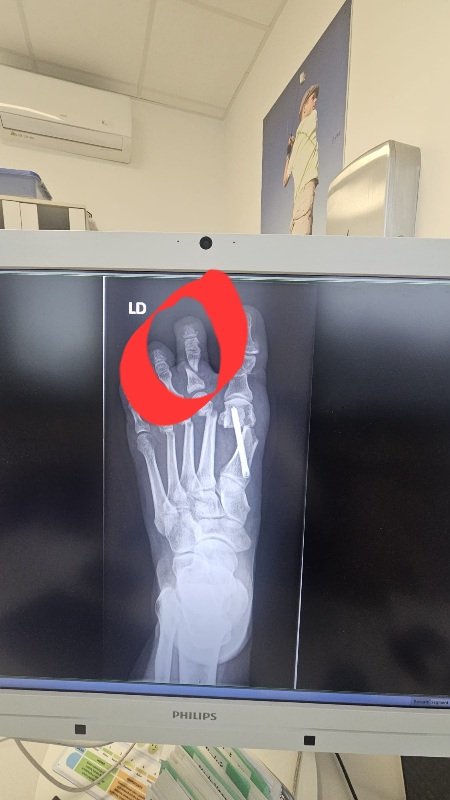

@vieramikloskova to áno,ja veľa vydržím ale toto je už moc....myslím ze je to týmto ze je tam zlomený ten prst

@bubu37 panebože, prečo ho máte zlomený?

@bubu37 ja že ste mali po operácii ešte nejaký úraz... To ste mali kladivkový prst a dr. cielene vytvoril zlomeninu a nechal tak????

@janka1677 ja som snímok videla až cestou z nemocnice. ..ked som sa ho na kontrole pytala co mam s tým prstom....tak ze mam ich tejpovať do pozície ako chcem mať prsty

@bubu37 mne žiadny snímok nedal. V podstate Vám dr. neodpovedal na otázku. Tejpuje sa vždy. Palec vždy a ak má pacient aj kladivkový prst, tak aj ten. Nepýtali ste sa na rovinu, prečo ho nechal zlomený a nepoistil skrutkou? Alebo ho prerezal s tým, že sa sám zrastie?

@janka1677 on mi to odfotil na mobil a pozrela som to až cestou domov,budem mu písať email

@bubu37 vy ste dopredu vedeli ze aj ten kladivkovy prst bude robit alebo to bola pre vas novinka lebo sa tak rozhodol pocas operacie?